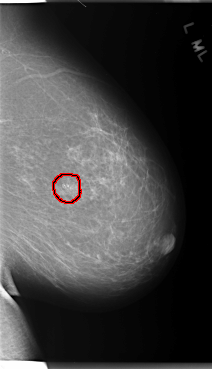

C_0106_1.LEFT_MLO

LEFT_MLO LINES 5904 PIXELS_PER_LINE 3384 BITS_PER_PIXEL 12 RESOLUTION 50 OVERLAY

FILE: C_0106_1.LEFT_MLO.OVERLAY

TOTAL_ABNORMALITIES 1

ABNORMALITY 1

LESION_TYPE CALCIFICATION TYPE PLEOMORPHIC DISTRIBUTION CLUSTERED

ASSESSMENT 4

SUBTLETY 5

PATHOLOGY MALIGNANT

TOTAL_OUTLINES 1

BOUNDARY